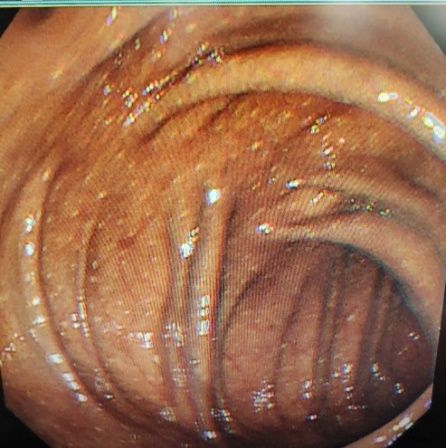

血液内科团队立即对黄玲进行了驱砷治疗,并且需要长期监测肿瘤的发生风险。医生们考虑到长期服用雄黄还可能造成结肠黑变病,还为她进行了肠镜检查。果不其然,肠镜检查显示,黄玲的整个大肠呈黑褐色,也就是结肠黑变病。